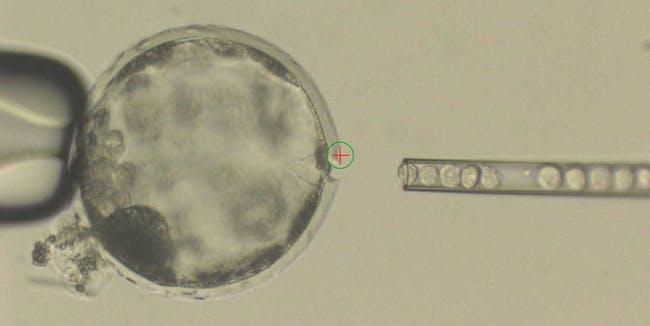

Tehnologija stem celic je prišla tako daleč, da znanstveniki lahko sedaj ustvarijo mini verzijo človeških možganov.

Poimenovali so jih organoidi ali mini možgani.

Medicinski etiki so zaskrbljeni o zadnjih odkritjih, saj to pomeni, da bi človeški mini možgani rasli v živalih.

Znanstveniki so poročali, da so možgani preživeli dva meseca, v enem primeru pa so jih celo povezali z živčnim sistemom in krvjo živali.

Mini možgane lahko zgradijo kar v laboratoriju, imajo pa enake lastnosti kot pravi človeški možgani.

Znanstveniki se prerekajo, saj niso prepričani ali so ti možgani živi, res pa je, da lahko žival z njimi živi.

Z vstavljanjem človeških možganov v živali seveda poraja etična vprašanja, saj se etiki bojijo, da bo to prišlo predaleč.